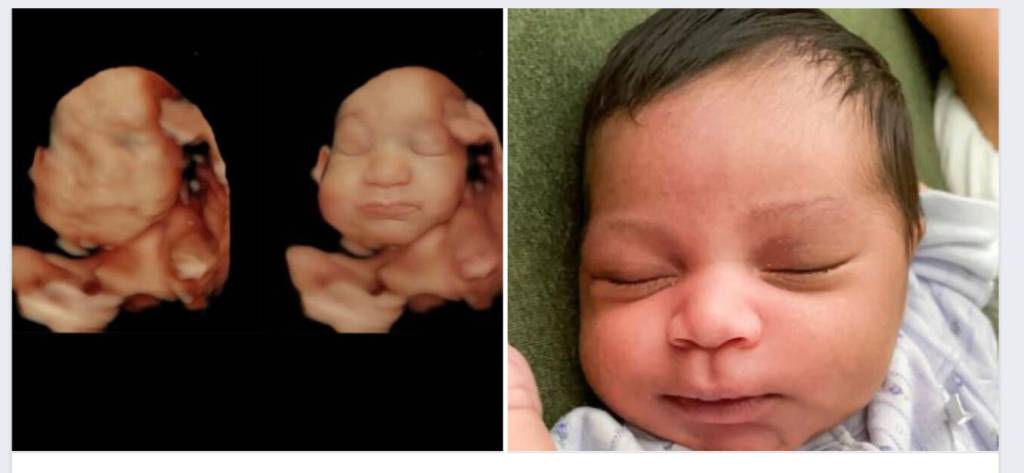

Many will remember the first time they ever saw a 2D ultrasound scan of their unborn sibling as a tender and exciting moment in their childhood. For some kids however, the excitement is quickly followed by a feeling of confusion as they try to make out the traits of a baby in what may seem more like bad chalk art.

Now, families on Whidbey Island can share with their kids the joy of seeing their child in detail, creating a stronger emotional connection with the baby. In May, Sonographer Kulvinder Kaur opened Island County Ultrasound, the only business on the island that offers color images and videos of fetuses in 3D, 4D and 5D, in addition to the 2D scans.

According to Kaur, 3D scans are still images, 4D scans come in both photo and video format, and 5D scans allow her to adjust the light to better see the baby. Unlike 2D ultrasounds, which show the baby’s organs and skeletal structure in black and white, these options make the baby look more realistic.

Located at 902 NE Center Street in downtown Coupeville, Island County Ultrasound also offers parents the chance to further enhance their baby’s images after the ultrasound session, adding more detail to their features as if they’re immortalized out of the womb. Sometimes, this makes for funny moments — like a baby sticking his or her tongue out.